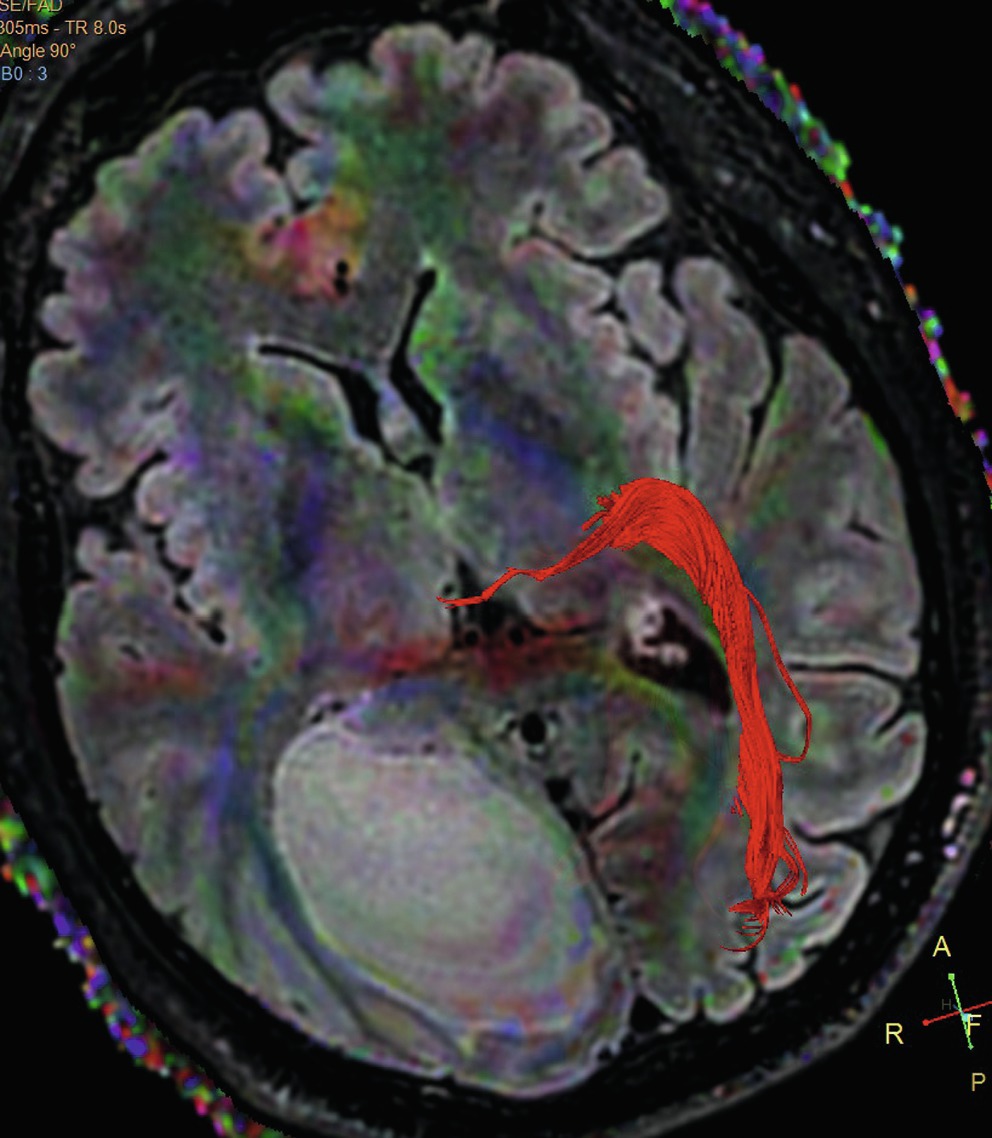

Tracking de fibres

Cette technique est utilisée depuis plusieurs années pour détecter des faisceaux de fibres de substance blanche, comme le faisceau corticospinal [10]. Elle repose sur le traitement informatique d'une séquence de diffusion avec une acquisition des images dans de nombreuses directions (32 à 64 dans le travail de l'équipe de Bertani)[11]. Le temps de séquence est d'environ 8 minutes mais peut aller jusqu'à 30 minutes. Le travail de reconstruction, long et complexe, est fait par le radiologue sur une console avec un logiciel dédié. Il consiste à «capter » les fibres allant d'un point à un autre. La tractographie des voies optiques se fait le plus souvent de manière fractionnée (nerf optique, tractus optiques, radiations optiques). Elle est très utile par exemple avant la chirurgie d'une lésion située sur le trajet des voies visuelles postérieures, dans le choix d'une voie d'abord qui les épargnera, quand ce trajet peut être repéré, ce qui n'est pas toujours le cas (fig. 2-36

Fig. 2-36

Tumeur occipitale droite: tractographie.Pas de repérage possible des radiations optiques droites. Voies visuelles postérieures bien visibles à gauche.

Source: C.Delmaire.

). Les essais de visualisation de petits faisceaux sont parfois décevants et restent difficiles en routine. Leur apport diagnostique est encore en cours d'étude (fig. 2-37

Fig. 2-37

Exemples de tracking de fibre.Image globale des faisceaux(a) du nerf optique (rouge) ; (b) du nerf optique (bleu) et des tractus optiques (mauves) ; (c) voies visuelles rétrochiasmatiques (jaune) ; (d) tractus jusqu'au noyau géniculé (jaune) et radiations optiques (vert).

et 2-38

Fig. 2-38

Tracking de fibre: nerfs optiques, atrophie optique gauche.

).